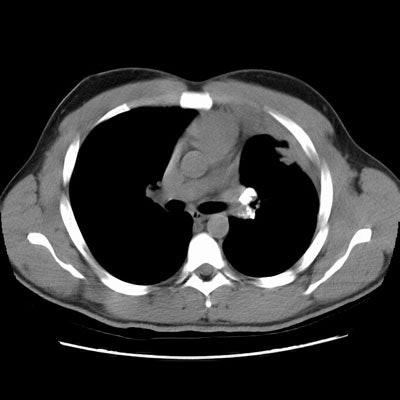

Rounded atelectasis in a patient with prior granulomatous infection

Asbestos related pleural disease is not the only cause of rounded atelectasis. The patient shown in the images below had a prior granulomatous infection with densely calcified left hilar adenopathy. There is extensive plerual thickening seen along the left anterior pleural surface. Rounded consolidated lung can be seen to abut this area of pleural thickening. Lung markings "swirl" into the area of abnormality. There is shift of the mediastinal structures to the left consistent with volume loss.